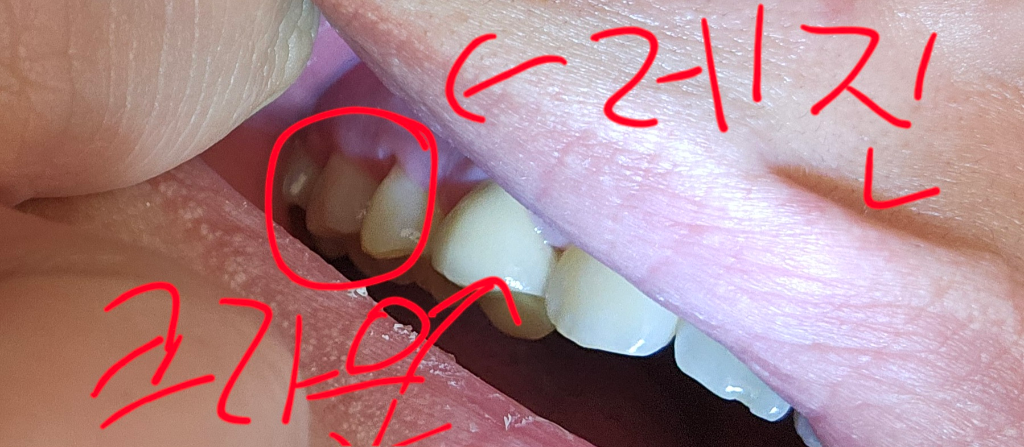

치경부 레진을 하신거 같습니다. 아마 치아가 많이 예민해진상태라서 치료를 하고나서 시린증상이 나타날수도 잇습니다. 시간이 지나면 괜찮아 질테니 너무 걱정하지마세요.

해당 사진만으로는 판단하기 어렵습니다. 어떠한 이유로 레진 등을 하고 있으며 무슨 치료가 이어지고 있는지, 그리고 치료 전의 상태는 어떠 했는지 현재 사진으로는 판단하기 어렵습니다. 지금으로서는 지속적인 불편감이 있다면 해당치과의 예약을 당겨서 방문하는 것이 필요합니다.